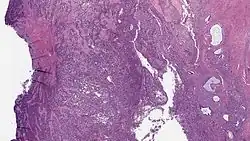

| Micrograph of a low-grade endometrial stromal sarcoma. H&E stain. | |

Low-grade endometrial stromal sarcoma consists of cells resembling normal proliferative phase endometrium, but with infiltration or vascular invasion. These behave less[3] aggressively, sometimes metastasizing, with cancer stage the best predictor of survival. The cells express estrogen/progesterone-receptors.

- Monotonous ovoid cells to spindly cells with minimal cytoplasm.

- Prominent arterioles. Angiolymphatic invasion common.

- Up to 10-15 mitotic figures per 10 HPF in most active areas.

- Tongue-like infiltration between muscle bundles of myometrium.

- May exhibit myxoid, epithelioid and fibrous change.

- May have foam cells or hyalinization in the stroma.